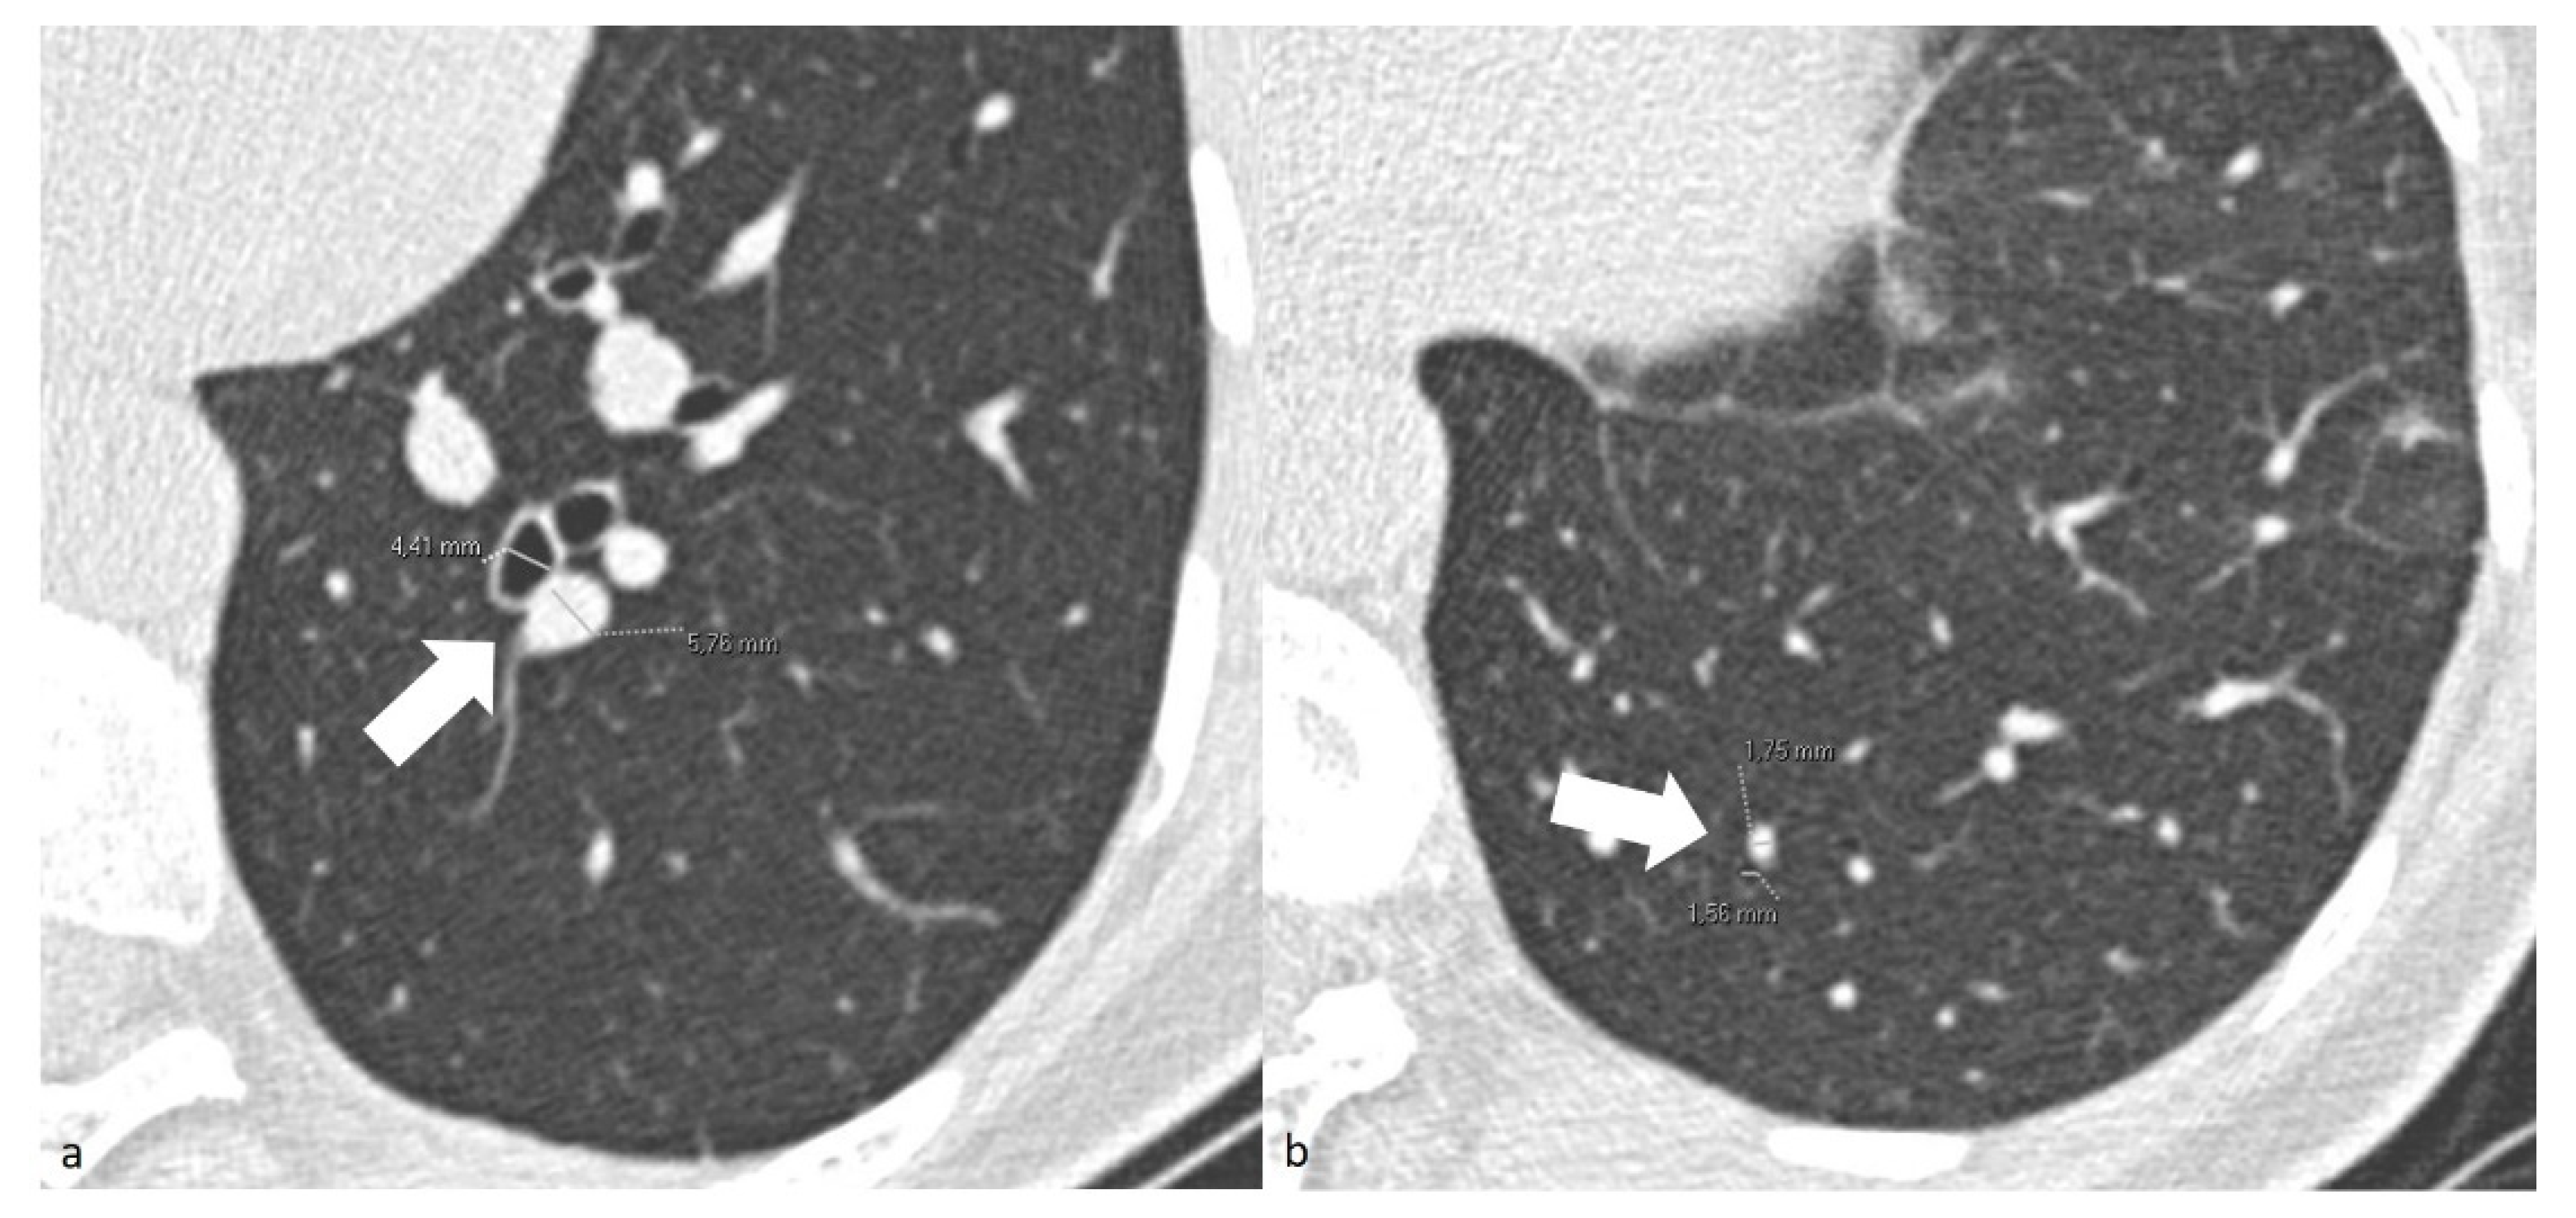

For patients in the COV-P, Bact-P, and Fung-P groups, the radiologist also measured the caliber of one segmental and one subsegmental branch of the pulmonary artery, together with their corresponding bronchial branches in the main area of lung opacification. To standardize the results, the radiologists measured the diameter only using the cross-sectional images of the segmental arterial branches 2 cm downstream of their onset and of the subsegmental branches at the level of the 7–8th generation. The adjacent bronchial branch diameter was measured, respectively, at the same level (Figure 1). To reduce inter-patient constitutional variability, the measurements of the healthy lung parenchyma were performed on the lower lobes.

Figure 1. (a) Chest axial CT images of a COV-P patient. Measurements of the segmental arterial (4.41 mm) and adjacent bronchial branches (5.76 mm) (arrow). (b) Chest axial CT images of a COV-P patient. Measurements of the and subsegmental arterial (1.56 mm) and adjacent bronchial branches (1.75 mm) (arrow) of healthy lung parenchyma of the lower left lobe.